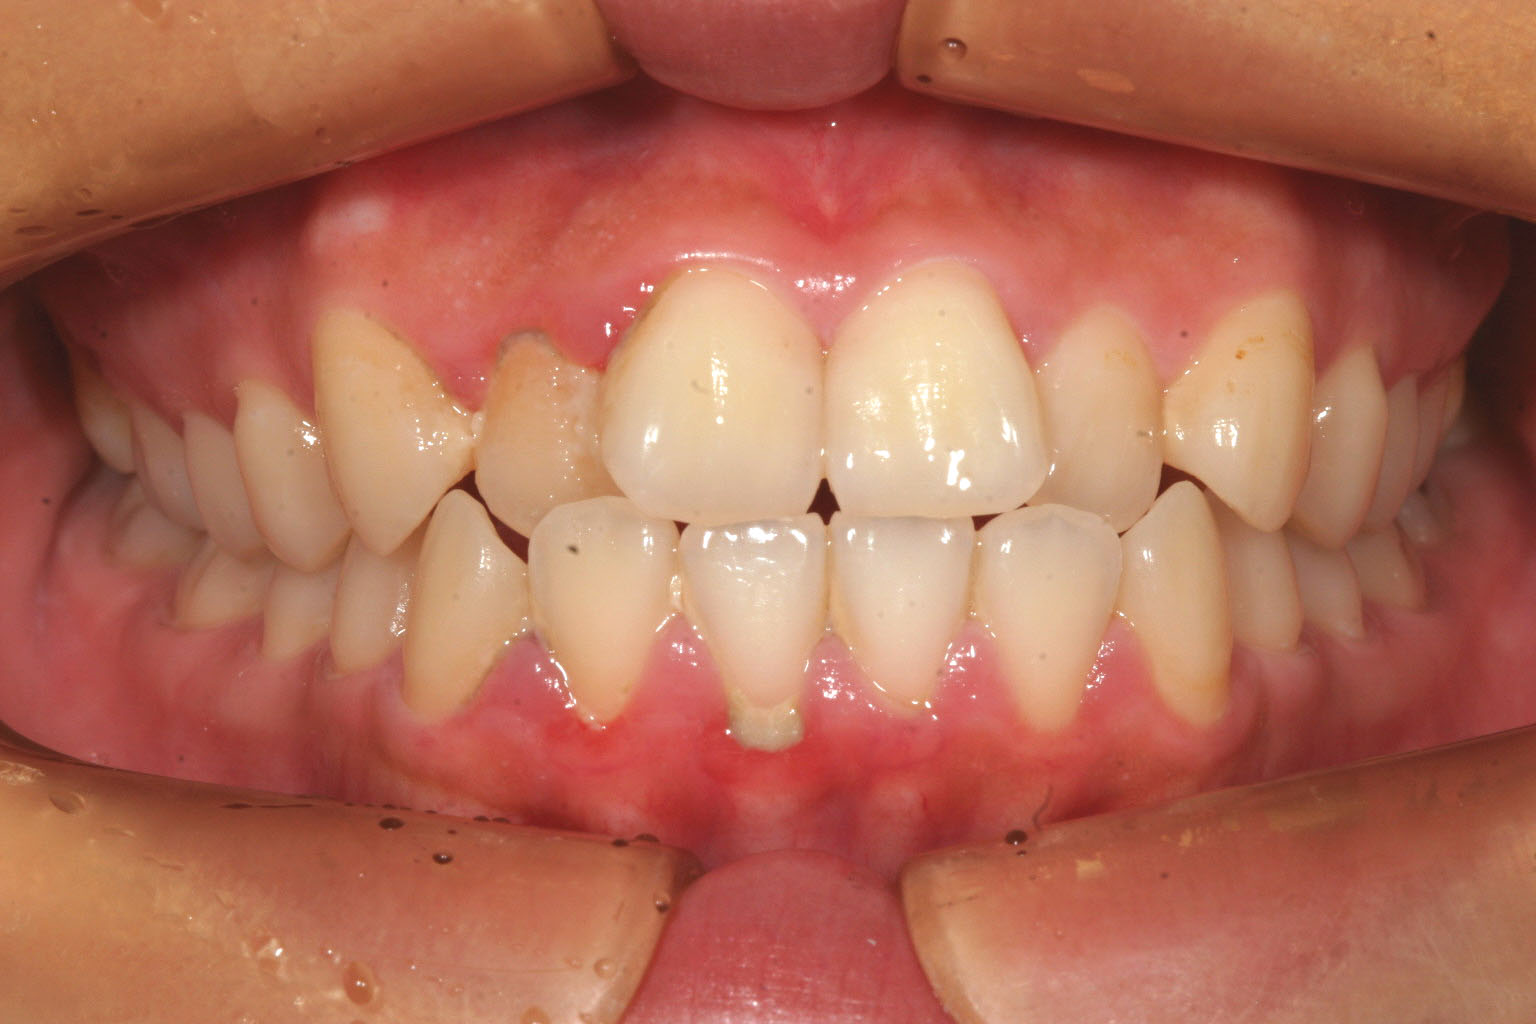

前歯 出っ歯 ガタガタ 二番目へこんでる 叢生 翼状捻転

かなりキツイ翼状捻転です。犬歯間幅径が狭いです。

二番目が入っている為少し出加減が気になります。

典型的な犬歯間幅径が狭い為の叢生(翼状捻転)です。